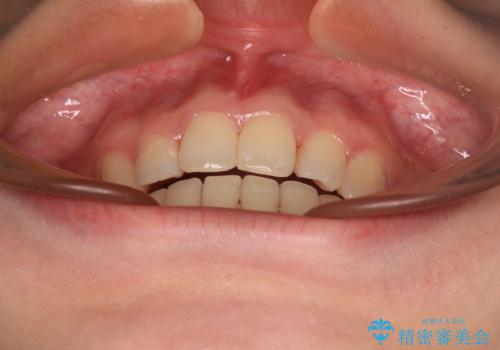

- 前歯のデコボコを気にして来院された患者様です。

前歯のデコボコはもちろん気になるところですが、舌の突出癖により上下の前歯に大きな隙間がある状態でした。